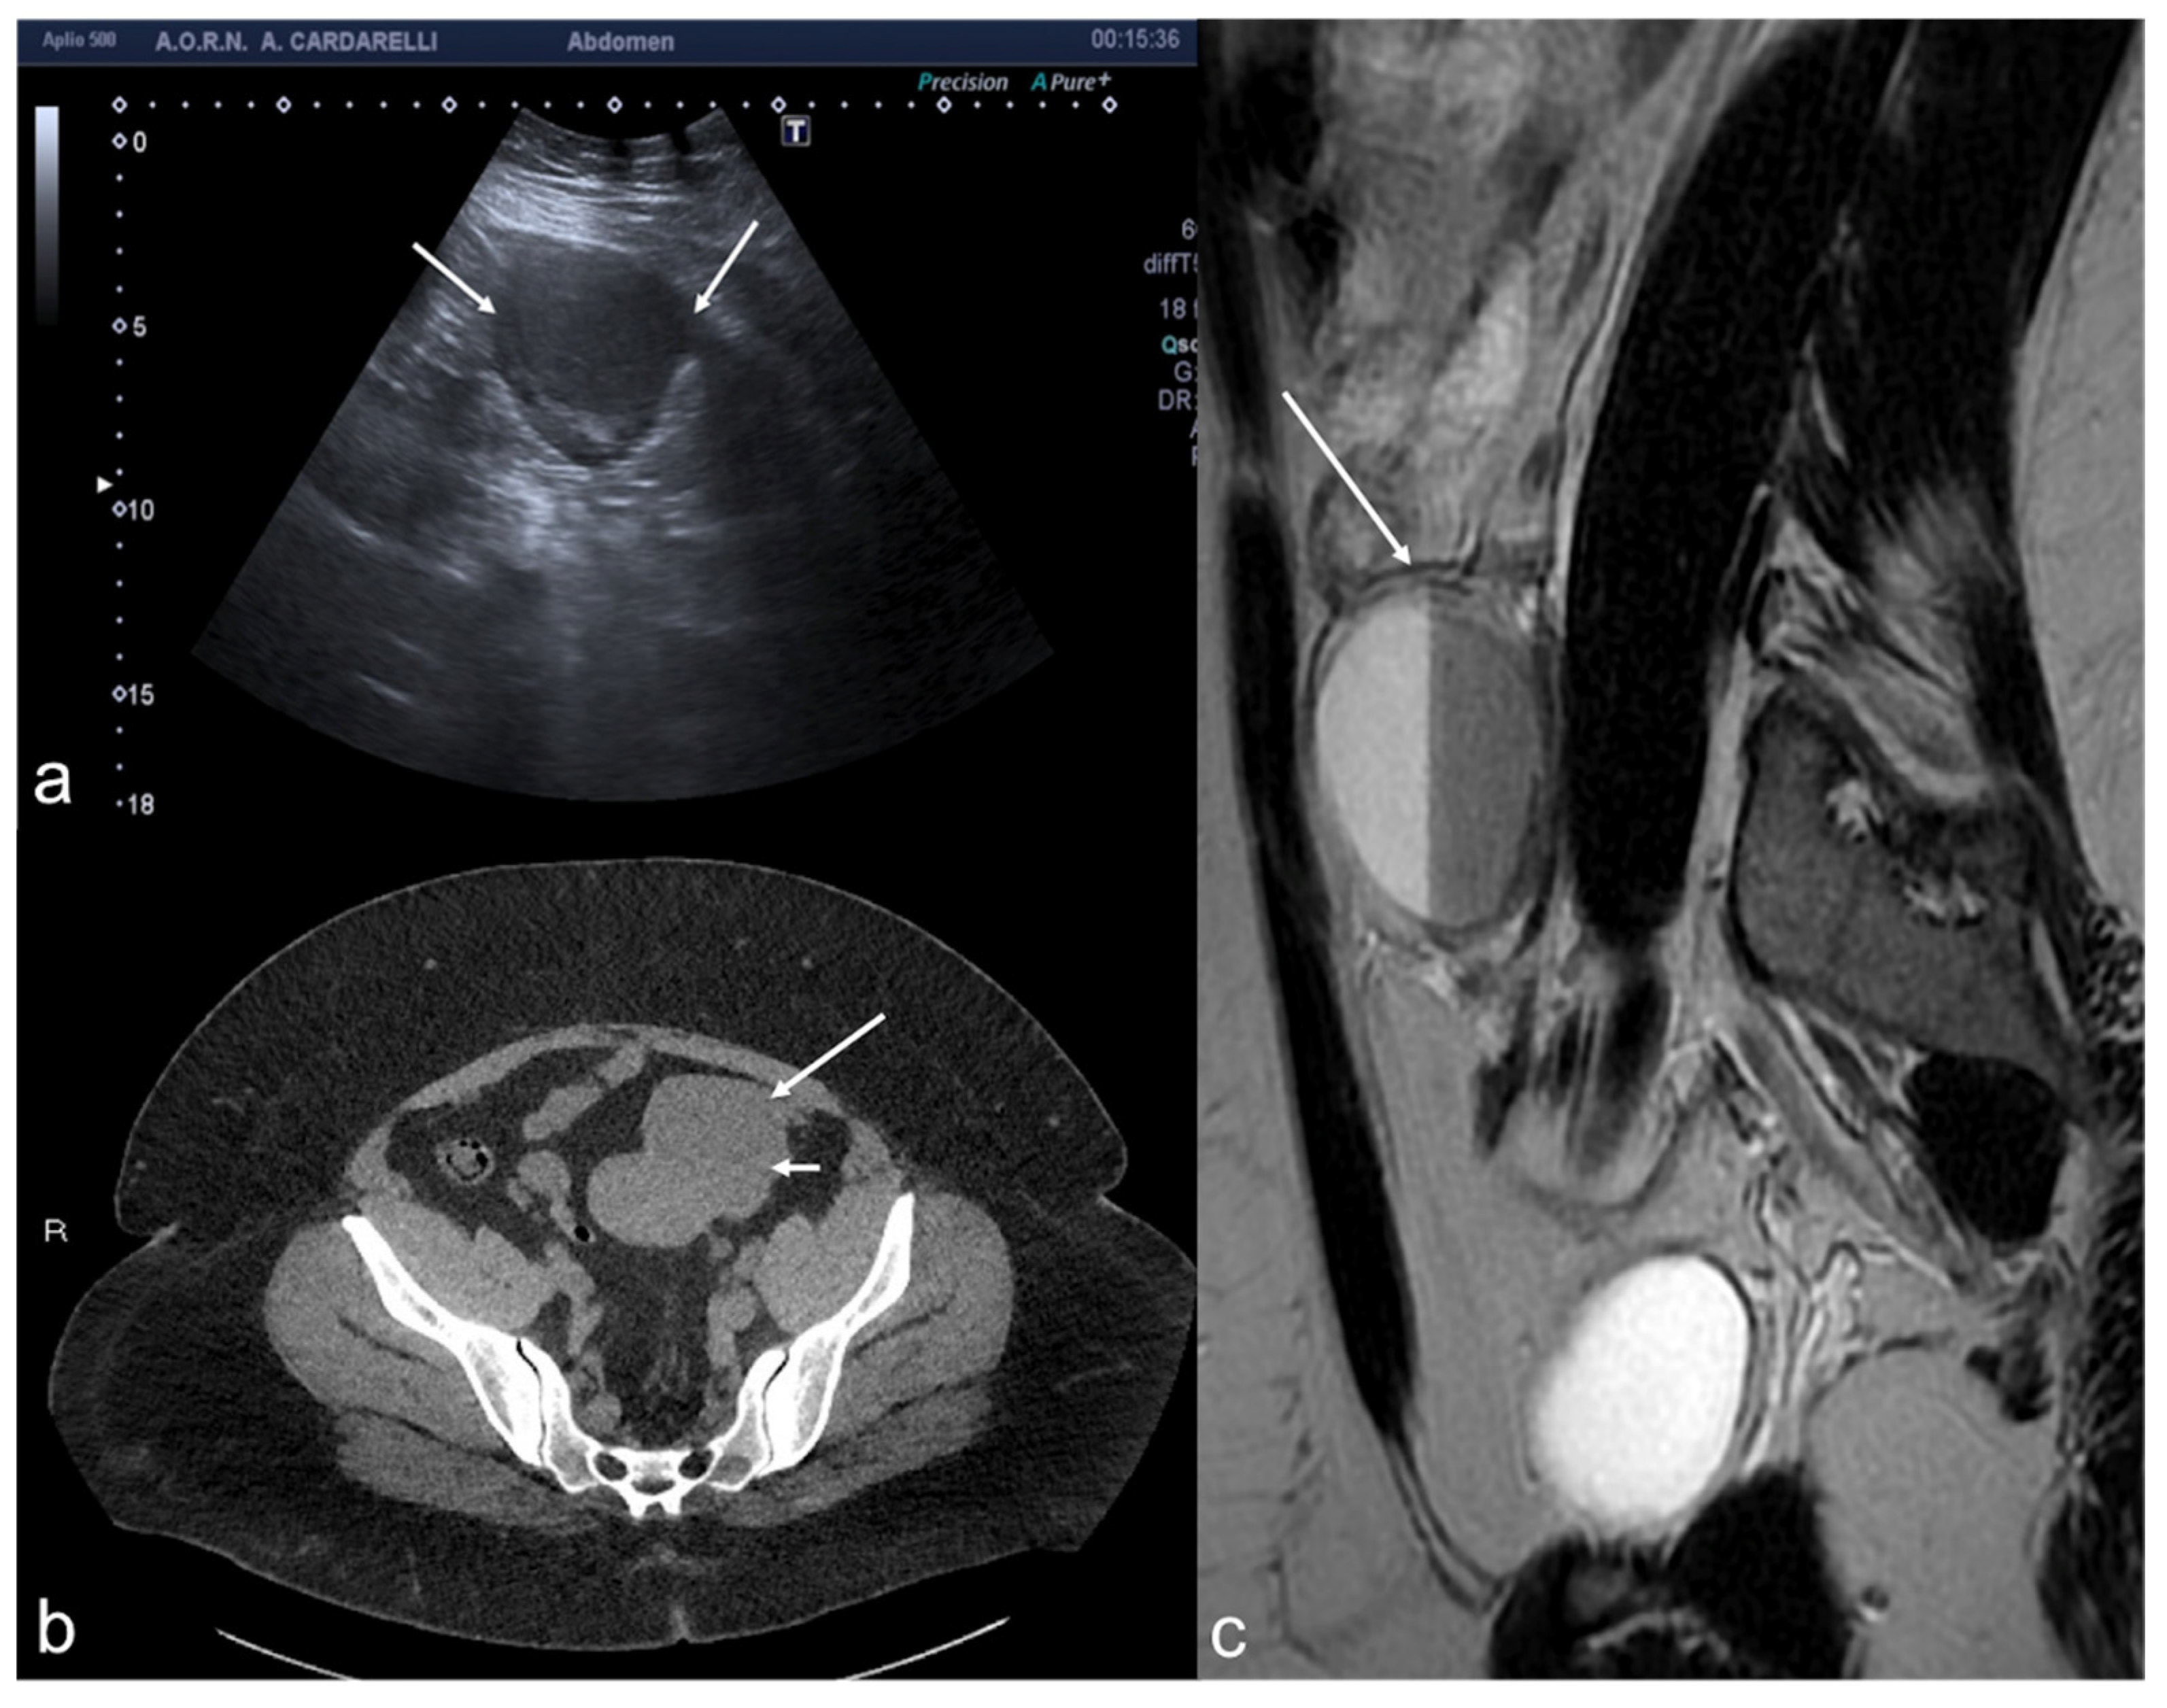

Figure 16. Thrombosis of the right gonadal vein. TSA–US scan of the left ovarian vein in axial (A) and longitudinal (B) view before delivery show the ovarian vein as a tubular structure with heterogeneous hypoechoic echotexture ((B) arrows), located superiorly to the ovary and anteriorly to the psoas muscle. Contrast-enhanced CT coronal image (C) was performed after delivery and confirmed the left gonadic vein thrombosis (red circle). Reprinted with permission from [46].

5.2. Thrombosis of the Gonadal Veins

Gonadal vein thrombosis is a condition that can occur in postpartum women or those undergoing pelvic surgery, with a referred incidence of about 0.18% of the general population [43,44]. Affected patients present with acute pain, often with fever and leucocytosis on laboratory examination. Thrombosis is observed more frequently on the right, probably due to the greater pressure present in the right gonadal vein than on the left, where the pressure would be protected by the retrograde flow of the left renal vein; the right ovary, the ipsilateral iliopsoas muscle, and the inferior vena cava are therefore frequently affected [1,43]. Uterine venous plexus thrombosis is also an unusual site of thrombosis often asymptomatic and incidental detected by TSV–US, which is decisive in the diagnosis and subsequent therapeutic choices [45]. US approach of gonadic vein thrombosis combines TSA–US and TSV–US. The latter is referred to the US method to explore the intere gonadic vein decourse and it is performed through transverse and longitudinal scans of the retroperitoneum showing an avascular structure with a tortuous tubular appearance, with adjacent anechoic or hypoechoic areas without any flow detection on the colour Doppler evaluation (Table 13) [46].

CT or MRI, both with contrast medium, should be carried out in the event of an uncertain diagnosis and to assess the extent of thrombosis (Figure 16). Furthermore, Time-of-flight (TOF) sequence is a non-invasive MRI technique that can be used to visualize thrombus as filling defects within gonadal veins, without the need to administer contrast [47].